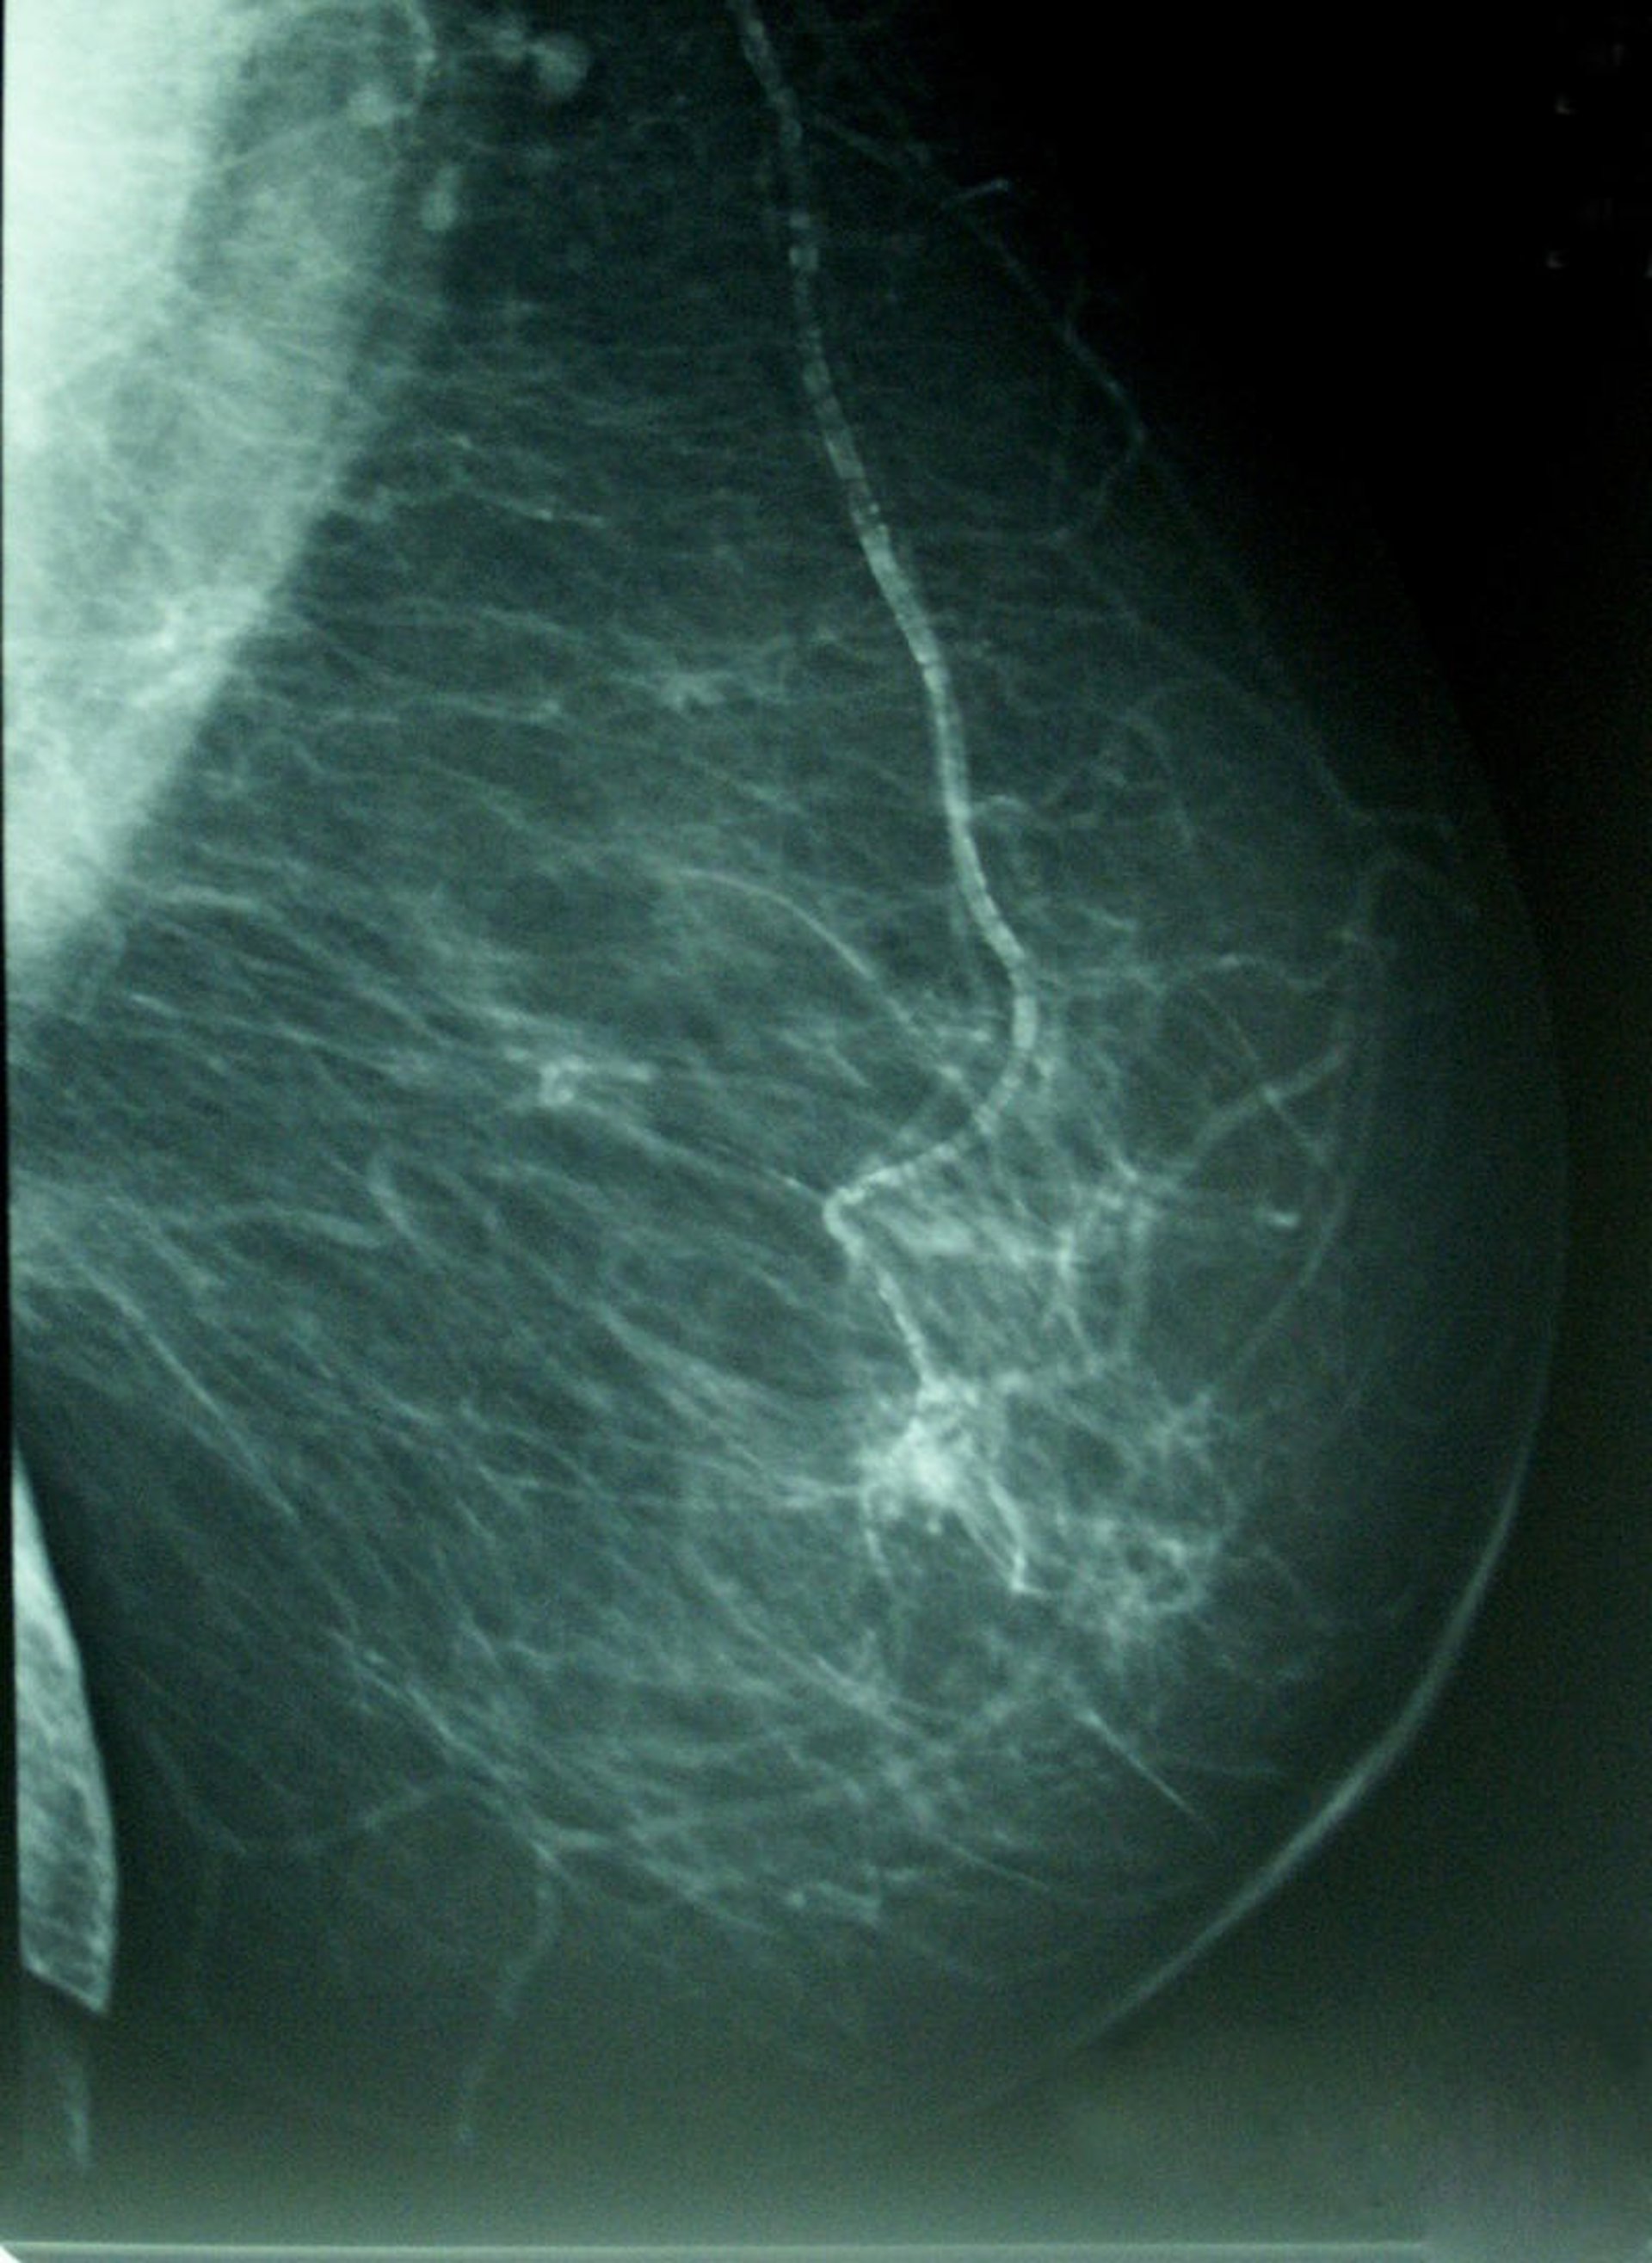

Cáncer De Mama, Densidad Mamográfica

Y es que, para Román Santamaría, efectuar esta prueba debe ser un objetivo, ya que es "la mejor manera para detectar a tiempo un cáncer de mama". Además, destaca que es un cribado "sencillo y no doloroso", y que no requiere preparación por parte del paciente.

En este sentido, el sanitario de USP San Camilo manifiesta que "mediante un diagnóstico precoz se pueden detectar los tumores mucho antes de que den síntomas, lo que facilita el tratamiento posterior". Así, estadísticamente se observa que la detección temprana del cáncer permite que la tasa de mortalidad se vea reducida a un ritmo de entre el 1 y el 2 por ciento anual.